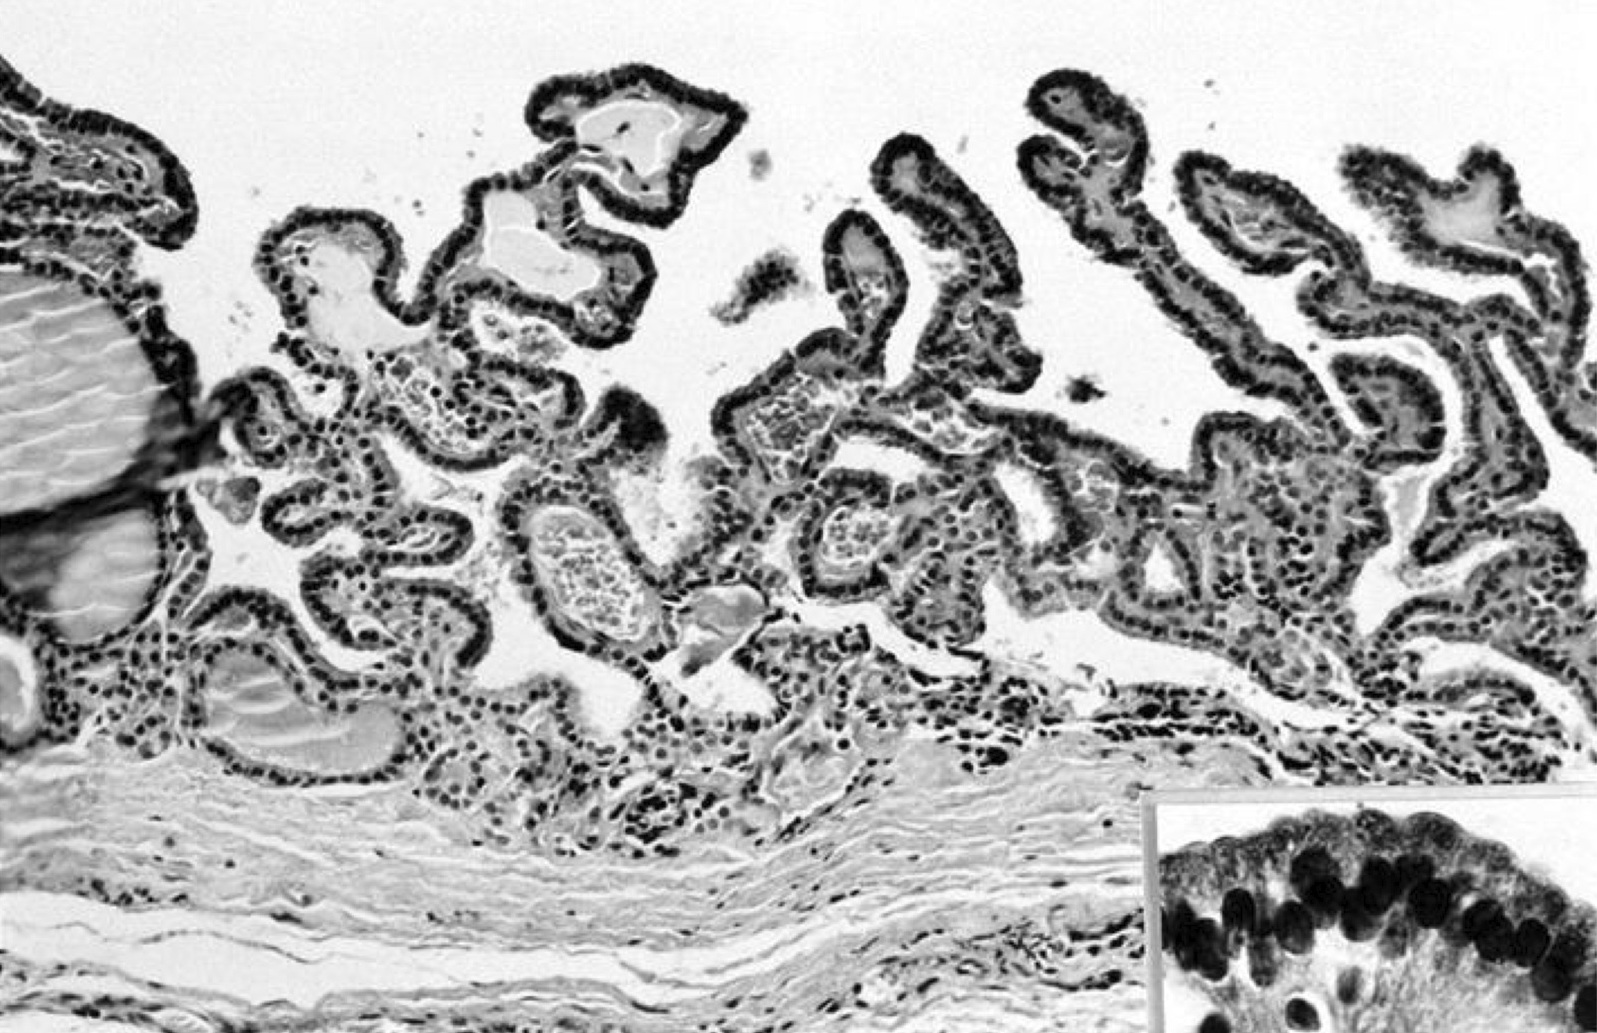

Microscopic (histologic) description

- Type of epithelial lining varies by site, and combinations of the types below can be seen in a single cyst (Head Neck Pathol 2013;7:50):

- Ciliated pseudostratified columnar (respiratory) epithelium in lower neck, perhaps due to its close proximity to upper respiratory tract

- Nonkeratinizing squamous epithelium in higher neck (near tongue and foramen cecum), also can be of metaplastic origin in inflammatory settings

- Stratified cuboidal epithelium at level of hyoid bone

- Very often the cyst is denuded of epithelium, at least focally, which reflects epithelial damage by inflammation

- Secondary inflammation is common, especially in sinus tract (J Pediatr Surg 1984;19:506):

- Intense lymphocytic infiltration, rarely arranged into lymphoid follicles

- Admixture of neutrophils (if the cyst is infected)

- Granulation tissue and fibrosis

- Thyroid follicles in the cyst / duct wall:

- Found in 30% - 60%, with higher yield on serial sections

- More common in infra- versus suprahyoid remnants, on the right paramedian side (Ann Otol Rhinol Laryngol 2000;109:1135)

- Seen in small irregular groups

- Thyroid epithelium may be normal or rarely hyperplastic or neoplastic

- Thyroid tissue often hidden by inflammation (Laryngoscope 2001;111:1002)

- Absence of thyroid tissue does not exclude the diagnosis of TGD cyst

- Mucous salivary-type glands can be found in the cyst wall, frequently in lingual and suprahyoid locations (Ann Otol Rhinol Laryngol 1996;105:996)

Microscopic (histologic) images

Contributed by Andrey Bychkov, M.D., Ph.D., Mark R. Wick, M.D. and AFIP

Images hosted on other servers: